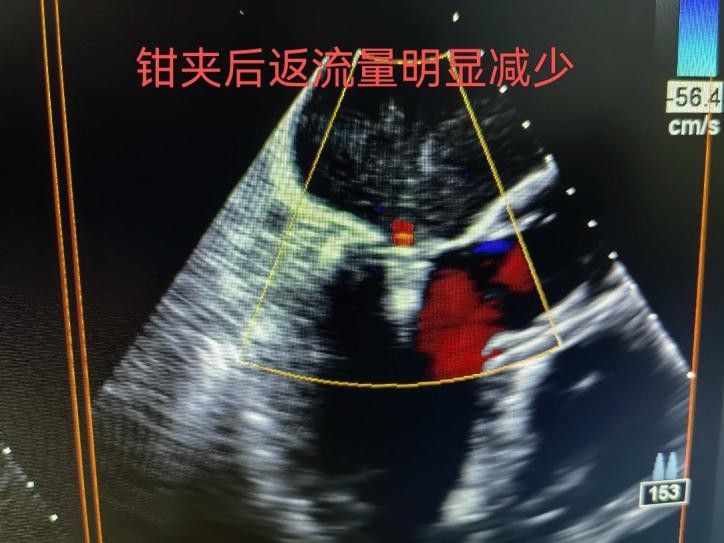

手術(shù)于11月4日下午進(jìn)行,通過(guò)股靜脈穿刺送入夾合器,在食道超聲實(shí)時(shí)引導(dǎo)下,精準(zhǔn)植入2枚瓣膜夾修復(fù)二尖瓣。整個(gè)過(guò)程歷時(shí)約2小時(shí),術(shù)中出血量?jī)H50ml。術(shù)后次日,患者即可下床活動(dòng),復(fù)查顯示EF提升至46%,二尖瓣返流面積縮小至3.0cm2,左心房縮小至66mm,胸悶、氣短癥狀明顯緩解。

2.精準(zhǔn)定位:在食道超聲和X線引導(dǎo)下,將夾合器送達(dá)二尖瓣位置,通過(guò)夾合病變瓣膜減少返流;